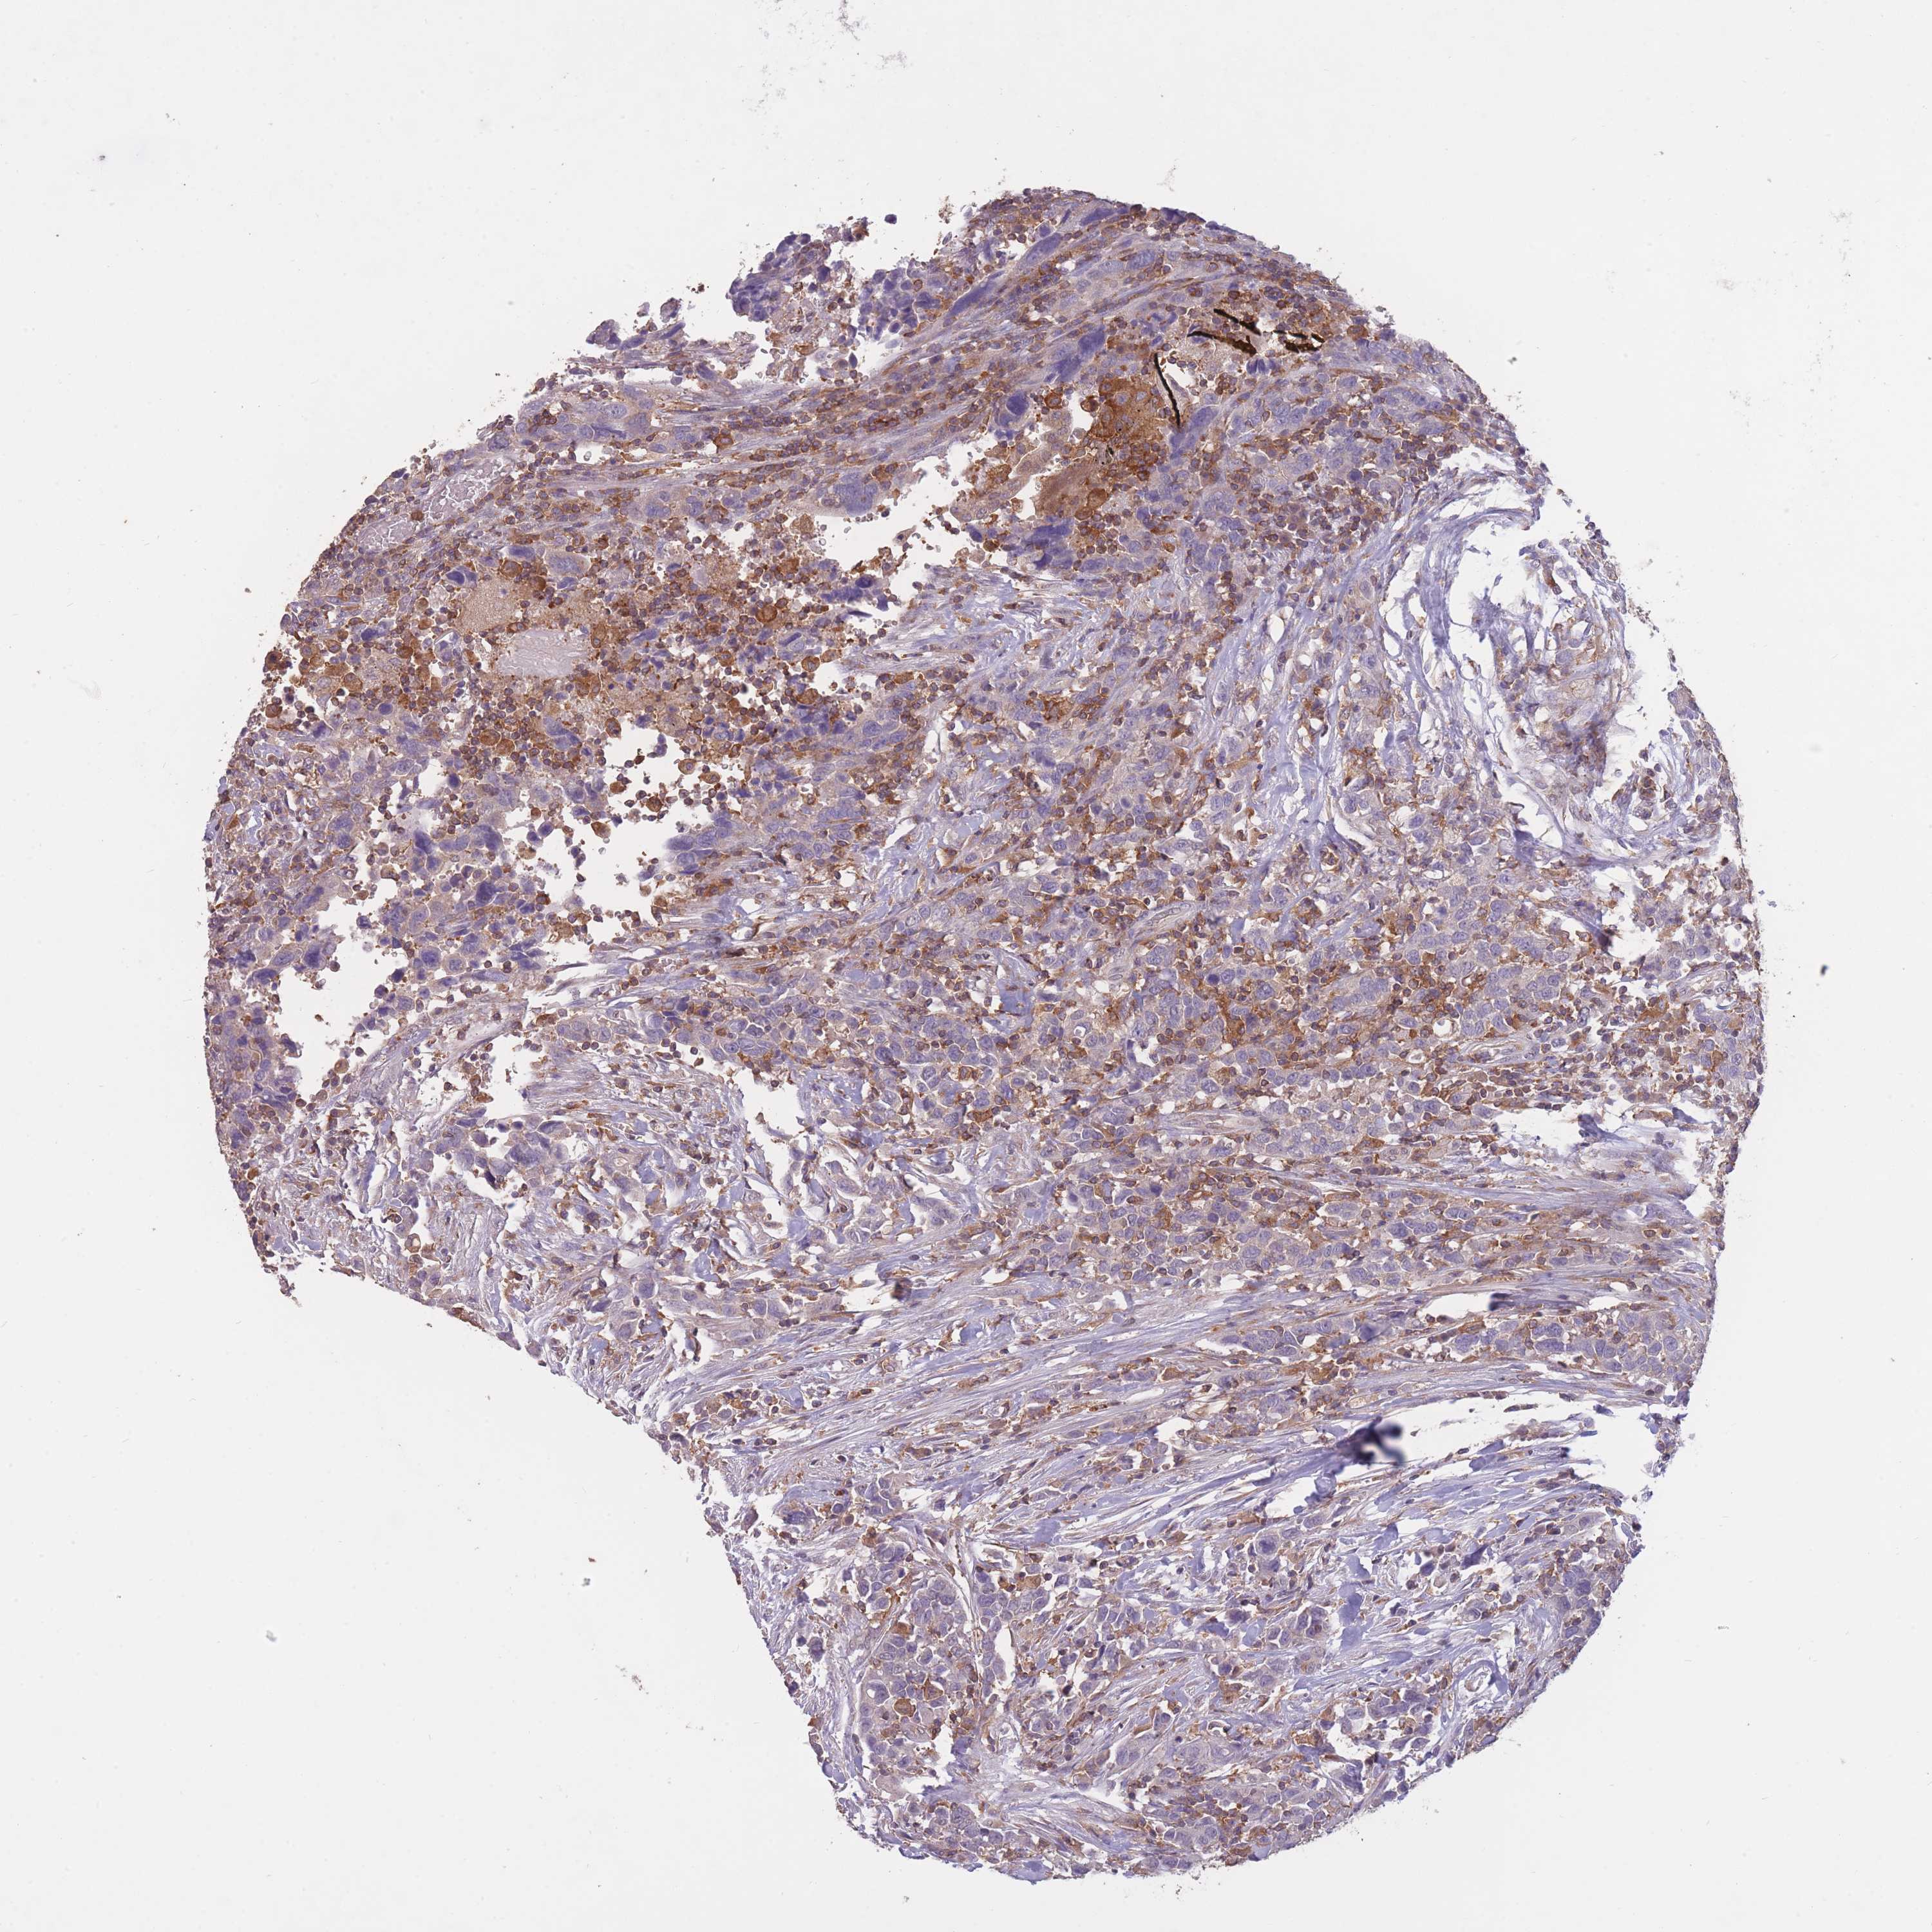

UROTHELIAL CANCER - Protein expressioni

A mouse-over function shows sample information and annotation data. Click on an image to view it in a full screen mode. Samples can be filtered based on level of antibody staining by selecting one or several of the following categories: high, medium, low and not detected. The assay and annotation is described here.

Note that samples used for immunohistochemistry by the Human Protein Atlas do not correspond to samples in the TCGA dataset.

Antibody stainingi

Antibody staining in the annotated cell types in the current human tissue is reported as not detected, low, medium, or high, based on conventional immunohistochemistry profiling in selected tissues. This score is based on the combination of the staining intensity and fraction of stained cells.

Each image is clickable and will lead to virtual microscopy that enables deeper exploration of all samples and also displays staining intensity scores, fraction scores and subcellular localization as well as patient and tissue information for each sample.

Antibody HPA042484

Antibody HPA045481

Staining

High

Medium

Low

Not detected

Intensity

Strong

Moderate

Weak

Negative

Quantity

>75%

75%-25%

<25%

None

Location

Nuclear

Cytoplasmic/membranous

Cytoplasmic/membranous,nuclear

Urothelial carcinoma, High grade

Urothelial carcinoma, Low grade

Urothelial carcinoma, NOS